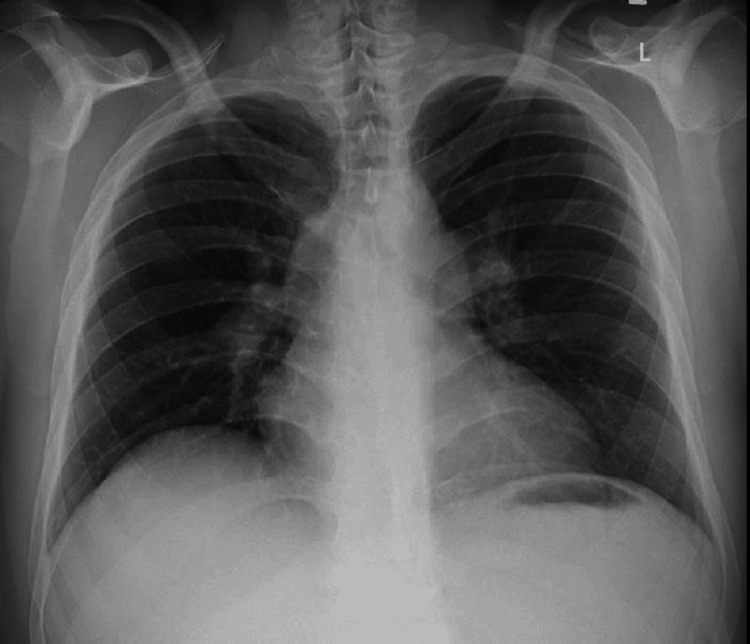

His D-dimer was elevated. The troponin-I, creatine kinase-myocardial band (CK-MB), and NT-pro-BNP were raised. An echocardiography was done, which revealed right atrial and ventricle enlargement with pulmonary artery pressure of 58 mmHg and no regional wall motion abnormality. The left ventricular ejection fraction was 50%-55%. The patient’s chest X-ray in posteroanterior view showed no focal lesion in the lung parenchyma (Figure 1).